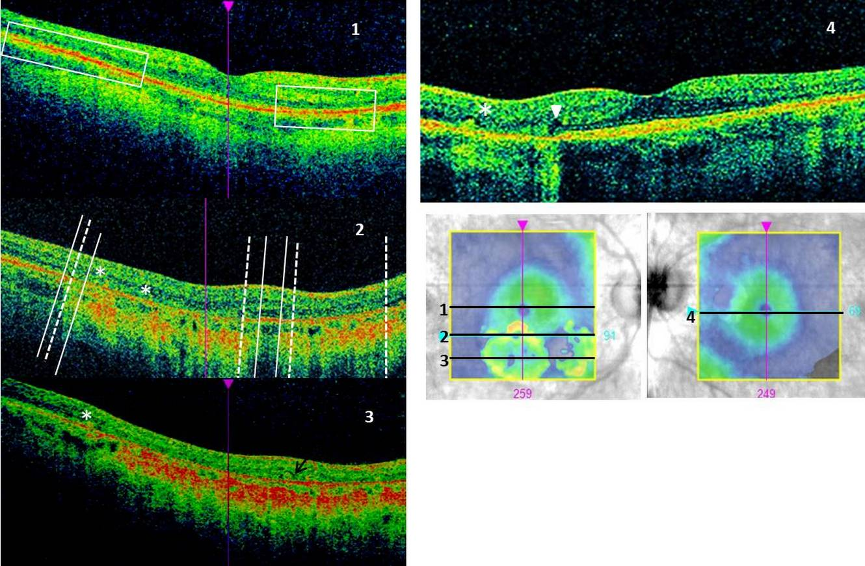

On OCT (Figure 3 [Fig. 3]) we noted loss of retinal pigment epithelium (RPE) and outer retinal layers (ORL) (photoreceptor-ellipsoid, external limiting membrane and outer nuclear layer), smaller in size compared to RPE loss, in the area of atrophy, with concomitant increased signal transmission to the choroid. We also found outer retinal tubulation and hyporeflective wedges. Outside atrophic areas granular irregularity at the level of the outer retina was visible as well as hyperreflective intraretinal foci. Also thinning of outer retina within atrophic areas was noticeable in the perifoveal macula. Average retinal thickness and cube volume of the scans was reduced at 246 and 226 µm and 8.9 and 8.1 mm3 in the right and left eye, respectively (normal range: 257.1–295.0 µm and 9.26–10.62 mm3) [17].

Figure 3: OCT scans

Right eye: 1–3 show slices from different levels: 1. foveolar: normal retinal profile, no cystoid macular oedema, but intraretinal hyperreflective foci visible as well as reduced thickness of outer retina and granular irregularity at its level (rectangular frames); 2. superior part of the atrophy: two atrophic areas separated with preserved retina. Extent of RPE atrophy (solid lines) is larger than outer retinal loss (dashed line); 3. central part of the atrophy: loss of RPE and outer retinal layers. Outer retinal tubulation marked with an arrow.

Left eye: 4. nasal area of atrophy with visible hyporeflective wedge (arrowhead).

On images 3 and 4 subretinal hyperreflective material is marked with asterisks. Also increased transmission to the choroid is present on the images along atrophic regions.